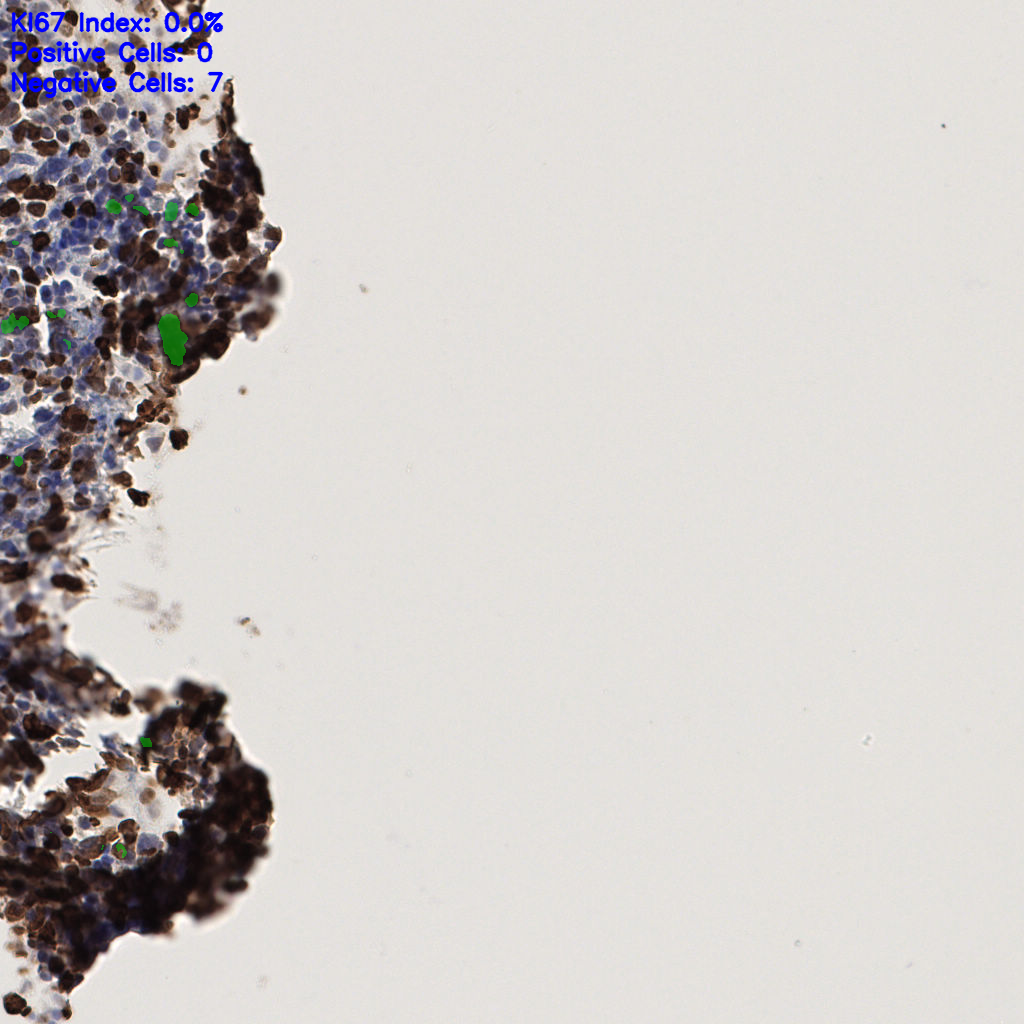

7.85%

Ki67 指数

阴 1104

阳 94

切片统计

总切片

1953

有效

288

已标记

有效率

15%

标记后

标记前